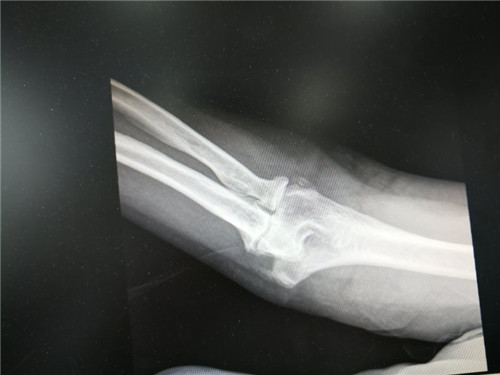

半年前,患者摔伤后在外院就诊,肘关节处外用膏药治疗效果不佳。一周前前来我院行X线检查提示:右肘关节骨性关节炎,门诊检查后以"右肘关节骨关节炎"诊断收住骨三科。

患者入院时查体右肘皮肤完好,轻度肿胀,右肘关节屈曲外翻畸形、肘关节前侧、后侧压痛,前侧可触及质硬包块,肘关节活动度50~100°。副主任医师胡洪波接诊后建议手术治疗,诊断为右肘关节骨性关节炎4期,经充分沟通后于1月3日与主治医师李政为患者施行"右肘关节镜下游离体摘除关节松解微创手术。"术后患者屈伸活动度明显改善,疼痛消失,生活基本恢复正常。